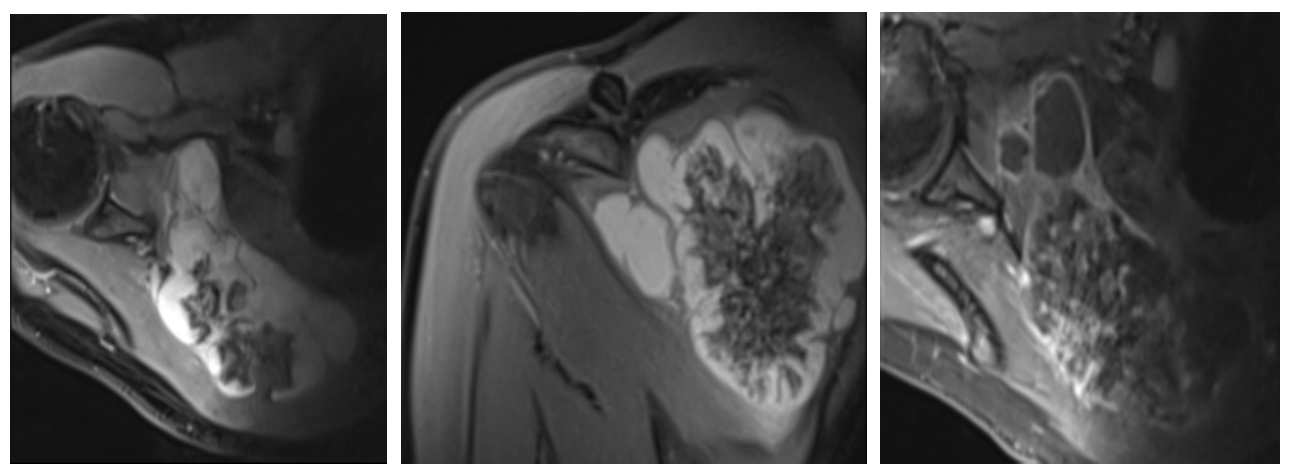

Ameliyat Öncesi: MR’da skapulada harabiyet, kıkırdak doku ve tümörün sınırları görünmekte.